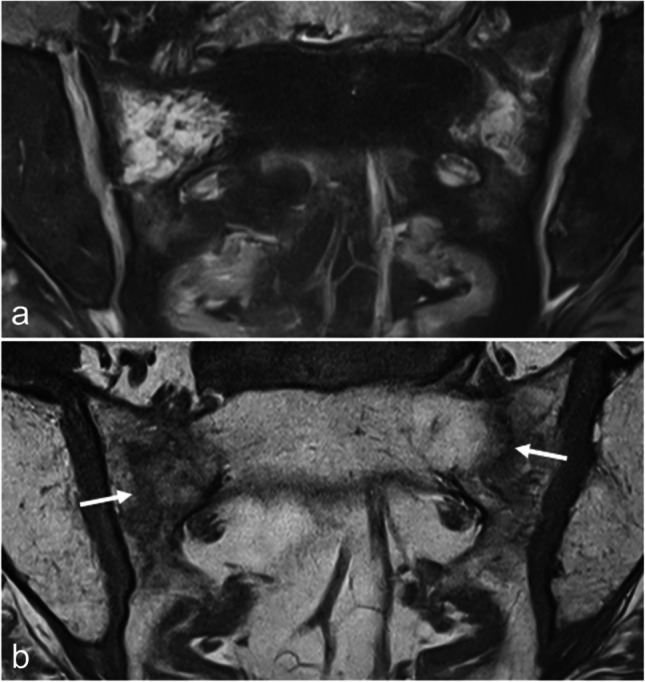

Magnetic resonance imaging of the sacroiliac joints (SIJ) is now frequently performed to detect subchondral inflammatory and structural changes in patients with early axial spondyloarthritis (SpA). However, similar changes can also occur in various other conditions, which may lead to the overdiagnosis of axial SpA. The aim of this article is to review the key imaging features of the most common disorders that may mimic inflammatory sacroiliitis, including mechanical changes and osteoarthritis, osteitis condensans ilii and pregnancy-related changes, other strain related changes, anatomical variants, pediatric SIJs, hyperostosis, infectious sacroiliitis, SAPHO syndrome, hyperparathyroidism, and sacral stress fractures.